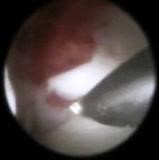

Рис. Работа в суставе под артроскопическим контролем

Метод малотравматичен. Производится два прокола через кожу в полость сустава. Через один прокол вводится артроскоп (специальный эндоскоп для осмотра сустава), через второй прокол – необходимый для работы в суставе инструмент. Современные артроскопы и инструменты очень миниатюрны, их диаметр составляет от 0,9 до 1,9мм, поэтому все манипуляции очень деликатны, а точки проколов видны только в первые дни после операции.

Первым этапом осматривается полость сустава, обнаруживаются патологические изменения в нём, после этого под визуальным контролем устраняются выявленные нарушения, а именно, рассекаются сайки, высвобождается суставной диск, удаляются флотирующие фрагменты тканей или сформировавшиеся кальцинированные тела. Если имеется воспалительная инфильтрация тканей, то эта зона коагулируется, что дает хороший противовоспалительный эффект. При необходимости может быть надсечено сухожилие латеральной крыловидной мышцы, и с помощью электро- или лазерной коагуляции обрабатываются связки биламинарной зоны. Это делается для уменьшения силы тяги мышцы и уплотнения связок, возвращающих диск в исходное положение.